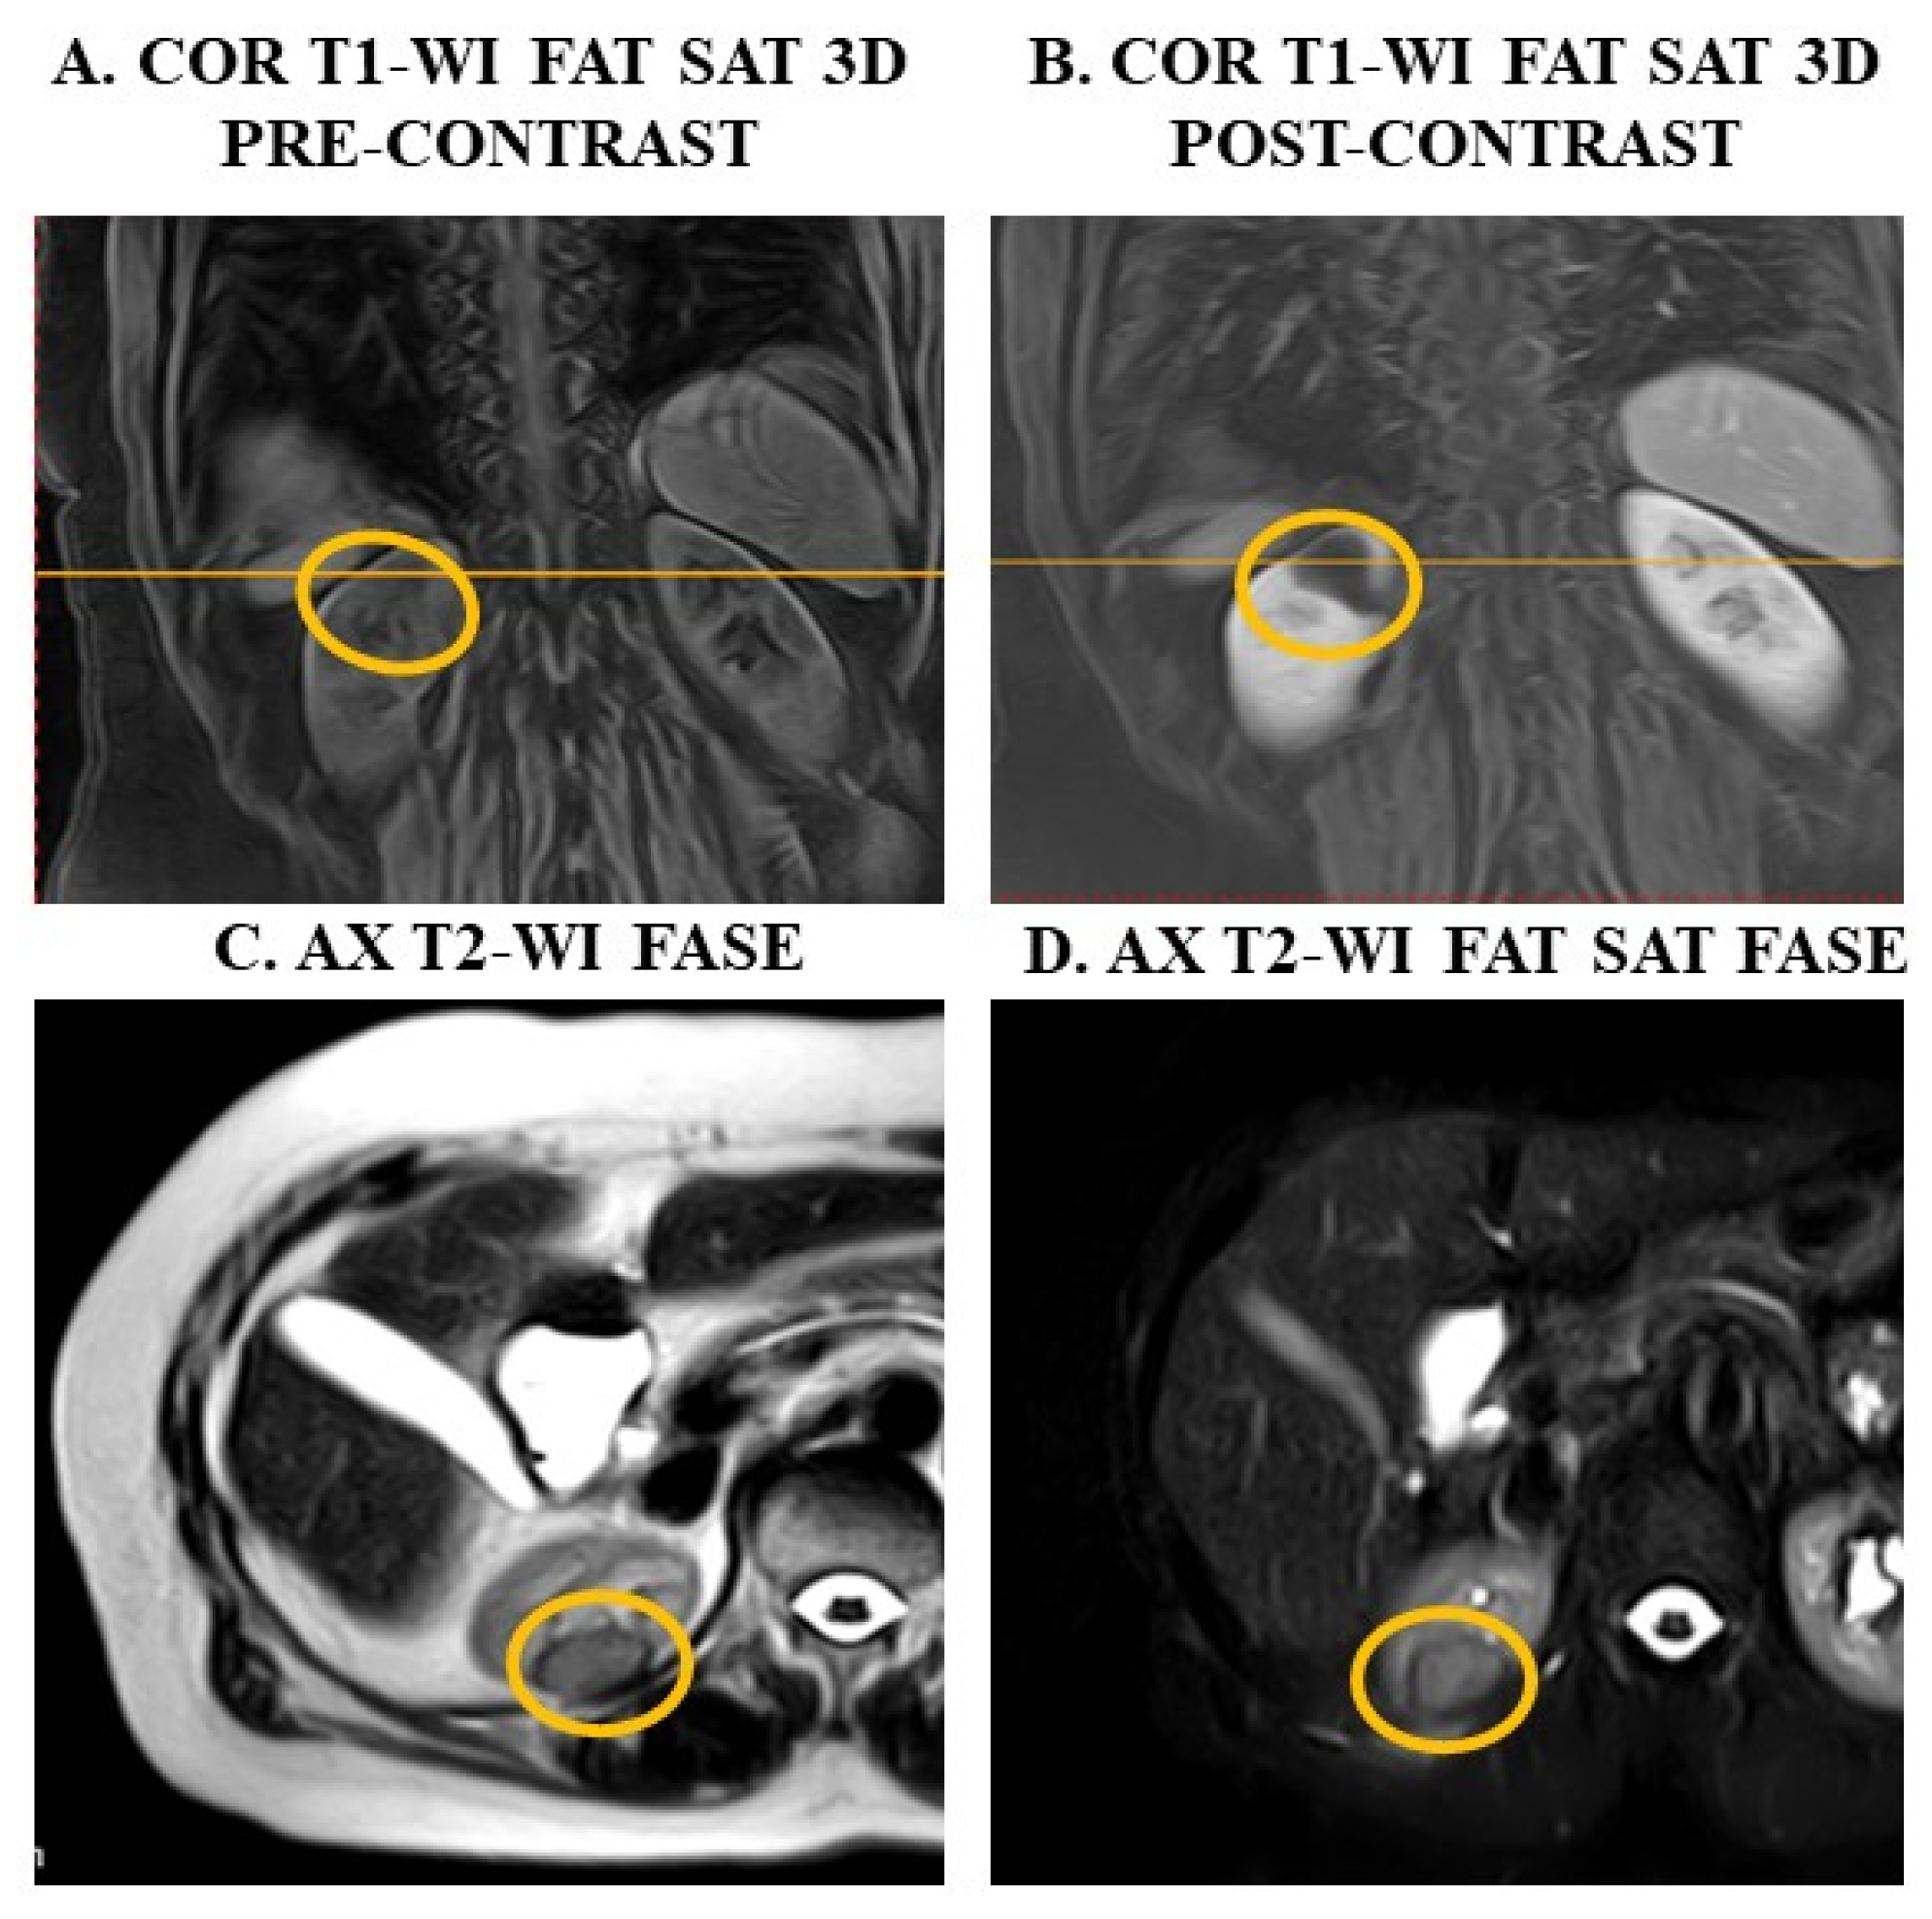

3. Examples of Applications of MRI Sequences in Upper Abdominal Analysis

4.1. The Use of MRI to Reduce Radiation Exposure in Oncology Patients